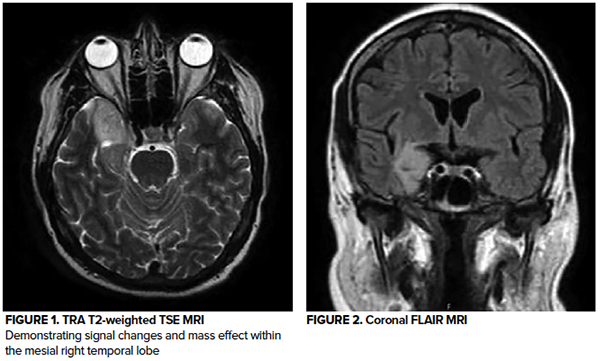

An MRI of the brain demonstrated an area of signal changes consistent with a mass effect in the mesial right temporal lobe. Neurology evaluated the patient and started him on levetiracetam 750 mg every 12 hrs. He was admitted to the hospital for further evaluation and symptom control.